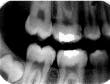

When the zygomatic process of the maxilla is superimposed on the roots of the maxillary molars (see Radiograph 4), another error occurs frequently with either technique. Too much vertical angulation will show this error in bisecting. Decreasing the vertical angulation by at least 10 degrees corrects it. With parallel technique, the key factor is improper placement of the film holder. Change the position of the film holder so the biting surface is flush with the occlusal and incisal surfaces.